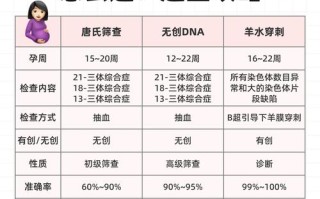

根据中国营养学会《中国居民膳食指南(2025)》和美国妇产科学会(ACOG)的建议,孕期适宜增重范围主要基于孕前BMI来划分:

| 孕前BMI分类 | 孕前BMI范围 (kg/m²) | 推荐总增重范围 (斤) | 平均每周增重(孕中晚期) |

|---|---|---|---|

| 体重过低 | < 18.5 | 22 - 33 斤 | 51 - 0.68 斤 (0.44-0.58 kg) |

| 体重正常 | 5 - 23.9 | 14 - 22 斤 | 37 - 0.58 斤 (0.32-0.50 kg) |

| 超重 | 0 - 27.9 | 7 - 14 斤 | 22 - 0.50 斤 (0.17-0.36 kg) |

| 肥胖 | ≥ 28.0 | 5 - 9 斤 | ≤ 0.22 斤 (≤ 0.17 kg) |